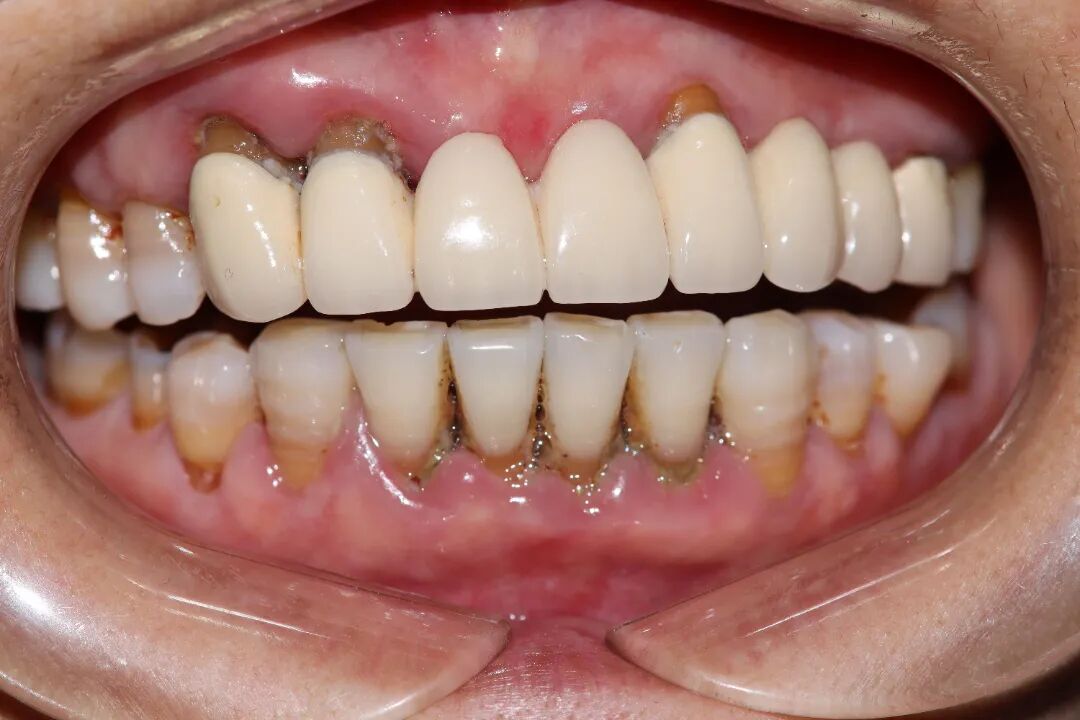

牙周内窥镜辅助下,给予牙周基础治疗2个月后,牙龈肿胀消退、色粉红、质韧,深牙周袋明显减少,探诊无再出血

治疗后